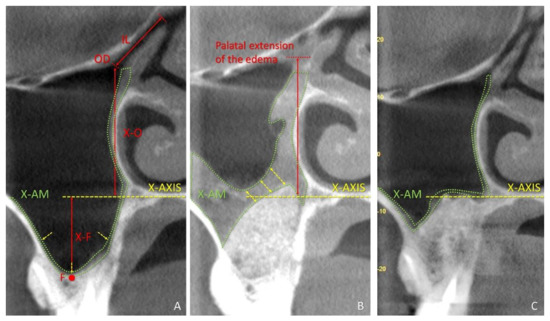

3.2. CBCTs Assessments